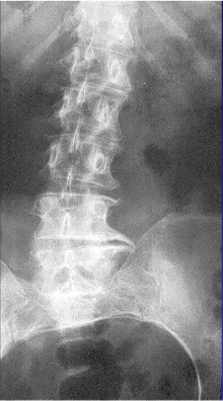

腰骶椎关节退变: